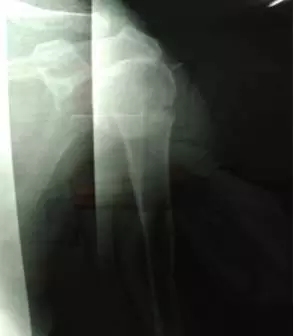

70多歲的鮑阿婆在家人陪同下來(lái)到上海大團(tuán)醫(yī)院就診。大團(tuán)醫(yī)院的醫(yī)生給鮑阿婆左肩部做了X線片檢查。片子拍出來(lái)竟然是左肱骨近端粉碎性骨折。外科頸,大結(jié)節(jié)都碎了,而且骨折端移位很?chē)?yán)重。

正骨科的虞杰主任、邵鵬及葉華磊醫(yī)生看到鮑阿婆的片子也是一皺眉頭,這么厲害的骨折,還真是少見(jiàn),而且移位這么嚴(yán)重,手法復(fù)位的難度也是相當(dāng)大的。不過(guò)患者的信任給了他們很大的動(dòng)力,即使困難也要盡力幫患者。

整復(fù)后復(fù)查X線片,骨折端位置良好。

整復(fù)前

整復(fù)后